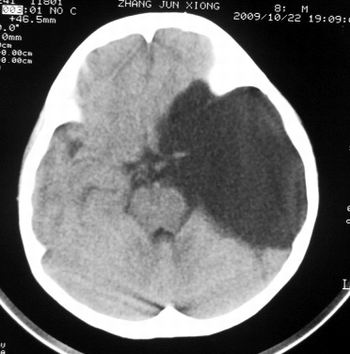

患儿,男,8岁,外伤2小时,无恶心、呕吐,四肢活动正常。既往无任何不适,智力发育正常。

典型的左中颅窝蛛网膜囊肿。

蛛网膜囊肿,需与表皮样囊肿鉴别。

典型的左中颅窝蛛网膜囊肿。最常见的发病部位,张力比较高,相应颅板受压变薄。赶紧治疗,脑组织的功能可能部分恢复。